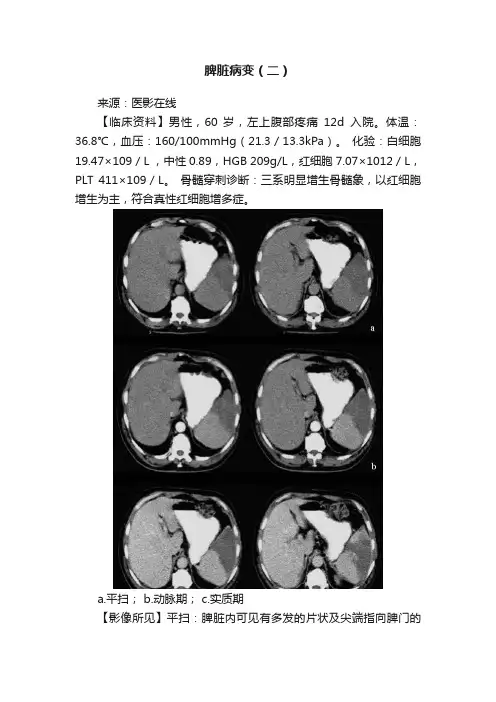

脾脏病变(二)来源:医影在线【临床资料】男性,60 岁,左上腹部疼痛12d入院。

体温:36.8℃,血压:160/100mmHg(21.3/13.3kPa)。

化验:白细胞19.47×109/L ,中性 0.89,HGB 209g/L,红细胞7.07×1012/L,PLT 411×109/L。

骨髓穿刺诊断:三系明显增生骨髓象,以红细胞增生为主,符合真性红细胞增多症。

a.平扫;b.动脉期;c.实质期【影像所见】平扫:脾脏内可见有多发的片状及尖端指向脾门的楔形低密度区,增强后扫描显示边界清晰,病变区大部分无强化。

【网友精彩发言】平扫基底位于脾外缘,尖端指向脾门,边缘尚清晰的三角形低密度影,增强后病灶无强化,典型的脾梗死。

(HLJnianLG)影像上典型的脾梗死。

临床诊断为:真性红细胞增多症,脾大,脾梗死。

(hejie)【后诊断】真性红细胞增多症合并脾梗死。

【点评】脾梗死是继发于脾动脉或其分支的栓塞,造成局部组织的缺血性坏死。

脾栓塞栓子的来源常见的是心脏病的血栓,肝动脉栓塞术后,胰腺癌,血液病如白血病、真性红细胞增多症,以及镰状细胞贫血所致的循环内凝血和血流停滞。

CT表现:典型表现是脾内的三角形或楔形低密度区,尖端指向脾门,基底位于脾的外缘,增强扫描病变区无强化,但轮廓较平扫时清楚。

也有一些不典型的梗死表现,呈多发的、不均的边界不清楚的小片或大片状低密度区。

大的梗死灶中央可以伴有囊性变。

陈旧性的梗死灶因纤维收缩,脾可以变小,轮廓呈分叶状,或见有钙化灶。